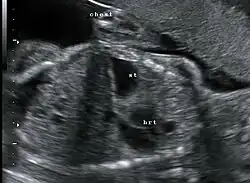

Die angeborene Zwerchfellhernie kann vor der Geburt im Ultraschall ab der 18. SSW dargestellt werden. Wird eine solche Diagnose vorgeburtlich gestellt, sollten weitere Untersuchungen (z. B. Kernspintomographie) in einem spezialisierten Zentrum erfolgen, um das Ausmaß an vorgeburtlicher Lungenschädigung einschätzen zu können, das die Prognose für das Überleben der Kinder und die angestrebte Erstversorgung wesentlich beeinflusst.